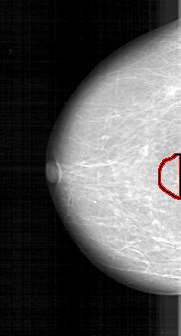

D_4125_1.LEFT_CC

FILE: D_4125_1.LEFT_CC.OVERLAY

TOTAL_ABNORMALITIES 1

ABNORMALITY 1

LESION_TYPE MASS SHAPE IRREGULAR MARGINS SPICULATED

ASSESSMENT 3

SUBTLETY 4

PATHOLOGY MALIGNANT

TOTAL_OUTLINES 1

BOUNDARY